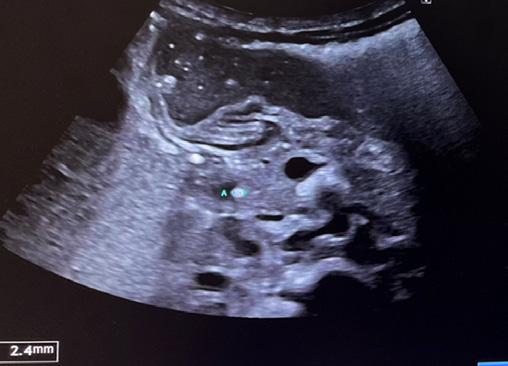

T. è una bambina nata prematura a 32 settimane. Trasferita in TIN per distress respiratorio da aspirazione meconiale, viene trattata con fototerapia per la scoperta di iperbilirubinemia. A causa della persistenza dell’ittero esegue esami del sangue per escludere patologie infettive, tiroidee e deficit di cortisolo. Screening neonatale e indici di emolisi negativi. Dosaggio dell’alfa-1 antitripsina normale [1]. Viene dunque trasferita presso il reparto di epatologia del Necker di Parigi per le cure del caso. Gli esami evidenziano una colestasi a GGT elevate e citolisi epatica (AST 227 U/L, ALT 202 U/L, GGT 516 U/L, BT 8,5 mg/dl BC 7,6 mg/dl). All’ecografia epatobiliare eseguita a digiuno da 6 h si evidenzia una colecisti non atresica [Figura 1], anzi, piuttosto distesa con all’interno sludge biliare, dilatazione della via biliare extraepatica [Figura 2] con evidenza di calcolo a livello della porzione distale coledocica [Figura 3] e dilatazione delle vie biliari intraepatiche, che presentano un aspetto irregolare. Assenza di polisplenia. Davanti alla presenza di un calcolo incuneato, viene avviata terapia iperidratante con aggiunta di UDCA, supplementazione vitaminica ADEC e vit K ev [2]. All’ecografia di controllo non si evidenzia più la litiasi biliare. Nuovo ricovero dopo 6 giorni per la persi-

Figura

Figura 1. Colecisti non atresica distesa con all’interno sludge biliare.

Figura 2. Dilatazione dilatazione della via biliare extraepatica di 6 mm.

Figura 3. Calcolo incuneato a livello della porzione distale coledocica.